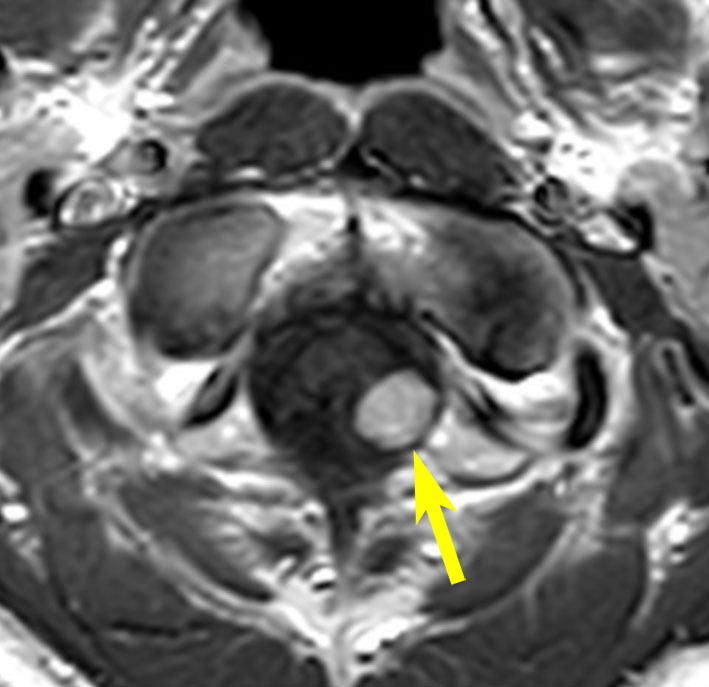

症例:小脳延髄角槽のもの,頸静脈孔へ少し入るもの

30歳くらいの女性に発生した無症状のものです。矢印のように拡大した頸静脈孔へ少し入っています。定位照射でもよかったかもしれませんが,若い女性なので手術しました。

脳槽部迷走神経根から発生したと考えて,外側後頭下開頭で摘出しましたが,予想外に延髄に近い部分の迷走神経から剥がせず,ほんの少し神経根の上に残しました。術後10年経ちますが腫瘍再燃はありません。聴神経腫瘍で顔面神経の上に薄く腫瘍を残すのと同じ考え方です。